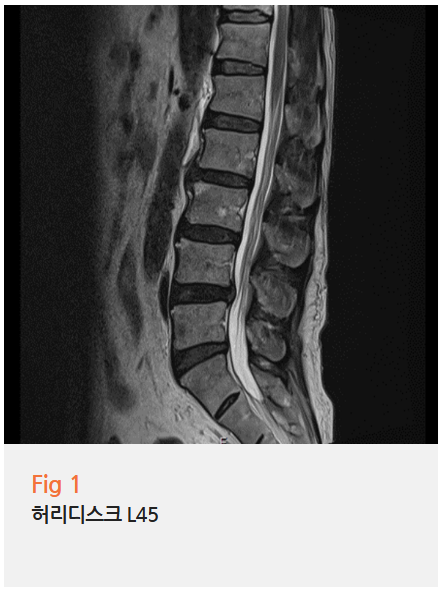

허리 MRI 결과

요추 4-5번 부위 추간판 탈출

(디스크가 신경을 누르고 있음)

즉, 환자분의 발가락 저림은

척추에서 나오는 신경이 눌리는 것 + 다리 혈관이 좁아지는 것

이 두 가지가 복합적으로 작용한 결과였던 거예요.

특히 왼쪽 발가락이 더 심한 이유도

왼쪽 혈관 협착이 더 심하기 때문이었고,

특정 발가락(2-3번째)이 시린 이유도

해당 부위를 지배하는 신경이

디스크에 의해 압박받고 있기 때문이었습니다.